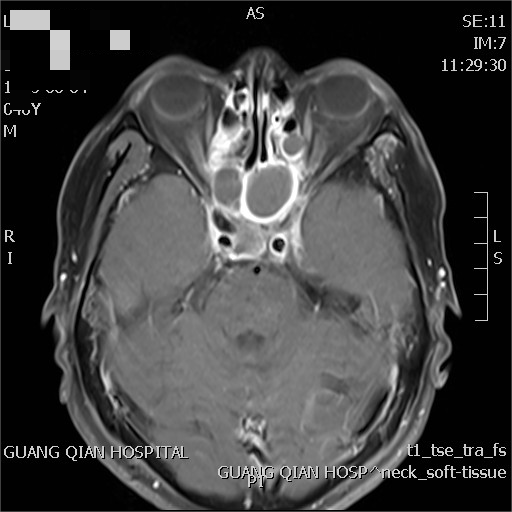

治療前后對(duì)比

林先生,因頭痛2年,近期前來(lái)我院診療,診斷鼻咽癌IV期。經(jīng)過(guò)姜教授指導(dǎo)放化療后,腫瘤基本消失。